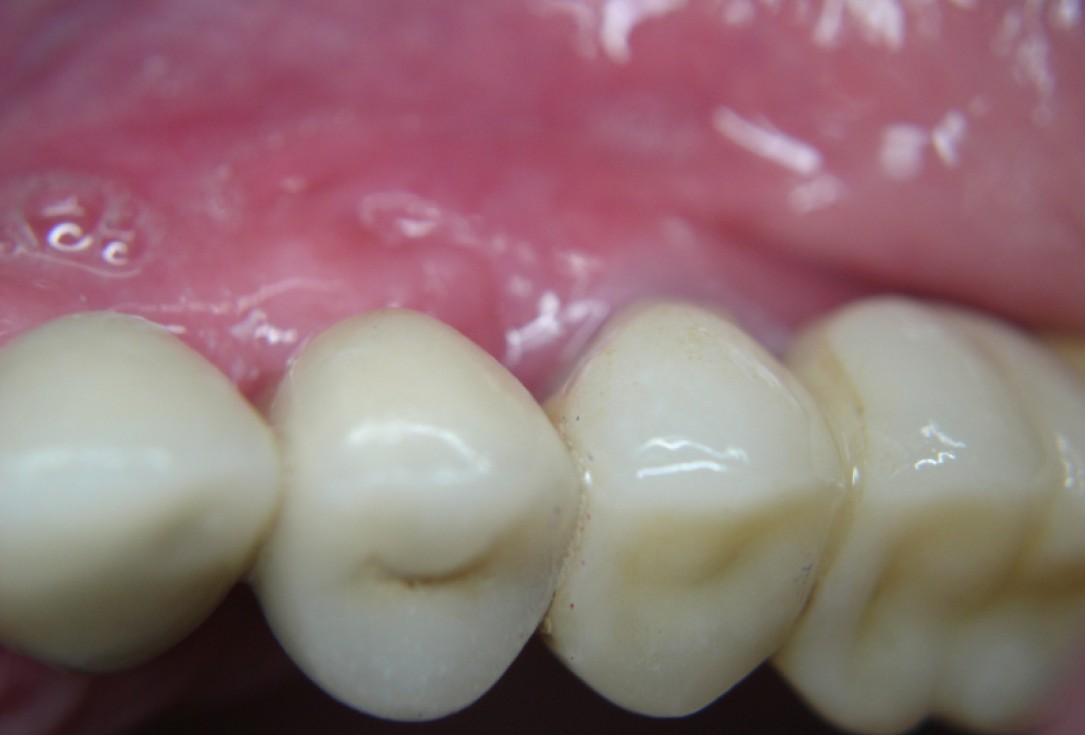

Three implants placed in a narrow posterior mandible